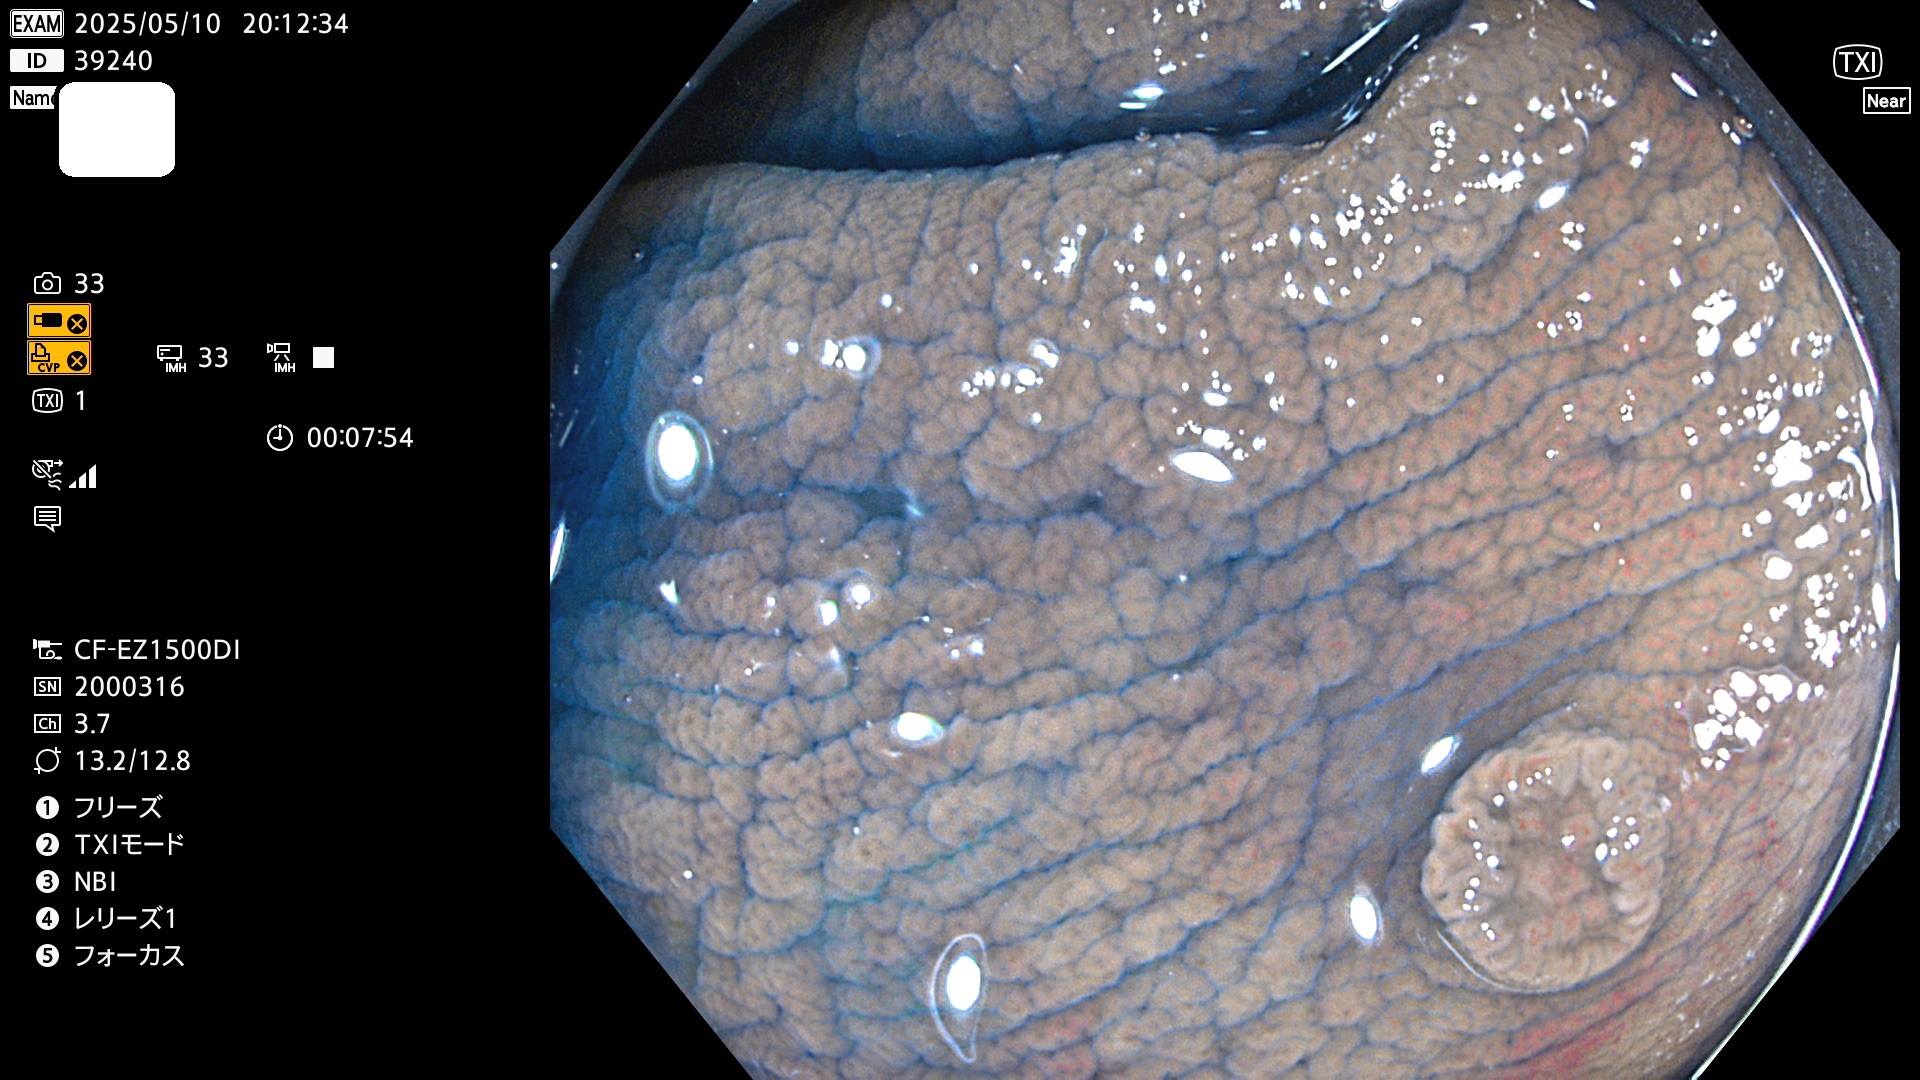

完全に平坦な物をUb、陥凹している物をUcと呼びます。Ubは認識が困難で、Ucはびらん(炎症)と紛らわしいために見落とされやすく、「内視鏡後・大腸癌」の原因になります。

抽出の対象期間 2025年5月8日〜5月11日の4日間(48件の検査)14個 (14/48=29%)